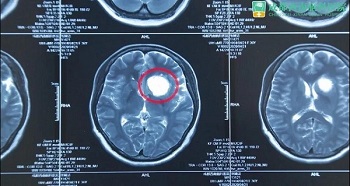

张女士 36岁 左前颅底肿瘤

患者1月前于贵黔国际总医院,行头颅MRI示:鞍上占位,脑电图:异常脑电图(左侧颞中央区局灶性改变) 。医院建议手术治疗,遂就诊于贵州医科大学附属医院,行头颅CT:鞍上池区域占位,考虑畸胎瘤可能,建议转院手术治疗。